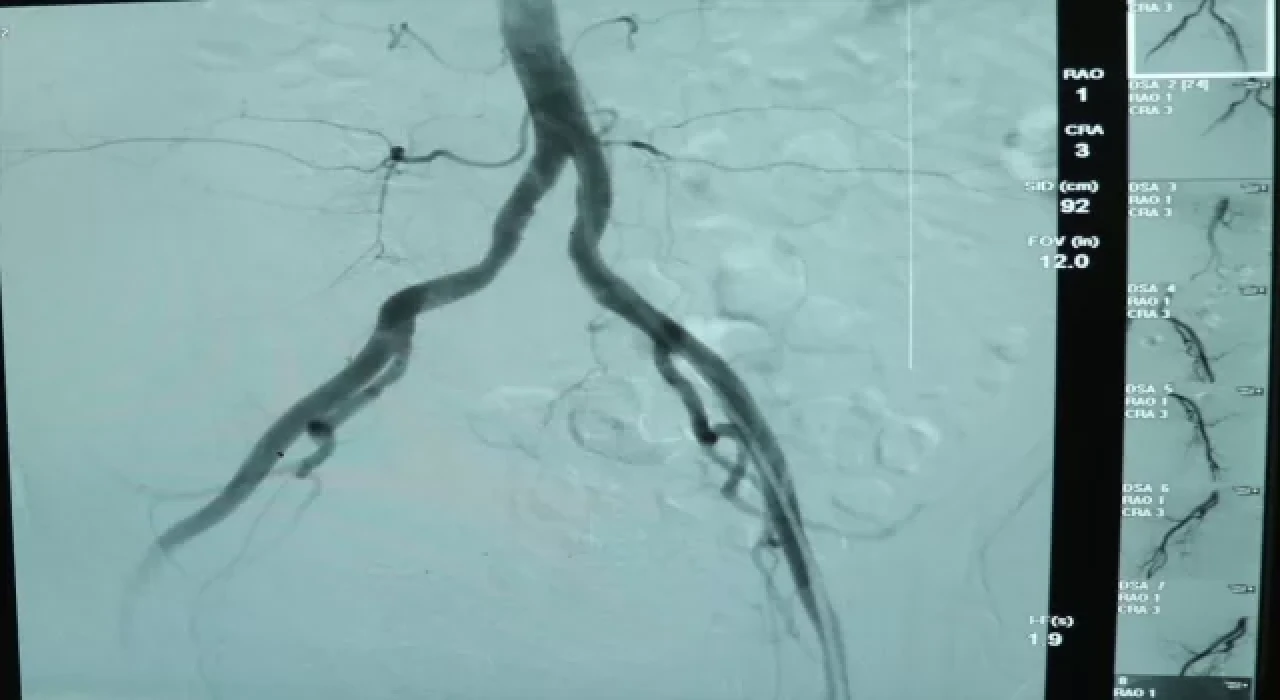

YALOVA (AA) Yalova'da hastaneye kaldırılan ve iç kanaması olan 77 yaşındaki kadın, "anjiyo ile embolizasyon" yöntemiyle tedavi edildi.

Kalp yetmezliği tanısıyla yoğun bakımda tedaviye alınan kadının tetkiklerinde, literatürde az rastlanır bir iç kanaması olduğu belirlendi.

Kanamanın ancak bölgesini tespit edebilen doktorlar, cerrahi müdahale yapılamayacak kadar küçük olan bu alana anjiyo yöntemiyle yaklaşık 4 saatte ulaştı.

Anjiyo ile embolizasyon yöntemi kullanılarak, damar özel bir maddeyle tıkanıp operasyon tamamlandı.

Kardiyoloji Uzmanı Dr. Mehmet Kocaağa, yaptığı açıklamada, tomografi çekiminde karnın arka tarafında yerini bilmedikleri bir damarda kanama gördüklerini söyledi.

Açık cerrahi ile tedavisinin mümkün olamayacağı için anjiyo yöntemini kullandıklarını belirten Kocaağa, "Kanamayı durdurmak işin kolay kısmı ancak tespit etmek zordu. Çünkü saç kadar ince bir damardan kanama oluyordu. Bütün damarları tek tek yakınlaştırıp mikro kateterle görüntüsünü aldık. Bunu tespit etmek yaklaşık 3,5 saatimizi aldı." dedi.

Uzman Dr. Fatih Rıfat Ulusoy ise anjiyo işlemini bu hastada damarı açmak için değil tıkamak amacıyla yaptıklarını kaydetti.

Müdahalenin ardından hastanın iyileşme sürecine girdiğini, bütün değerlerinin normale döndüğünü vurgulayan Ulusoy, "Bu hastamız için cerrahi şansımız yoktu. İlaçla da durduramadık. Tansiyonu düşmeye başlamıştı, şoka giriyordu. Tek çaremiz buydu ve hızlı şekilde görüntülemeyi yaparak kanamayı durdurduk. Hastamızın genel durumu gayet iyi. Sağ kalça kaslarını besleyen bir damar bu. Onun bu şekilde kanaması çok çok düşük bir ihtimal." diye konuştu.